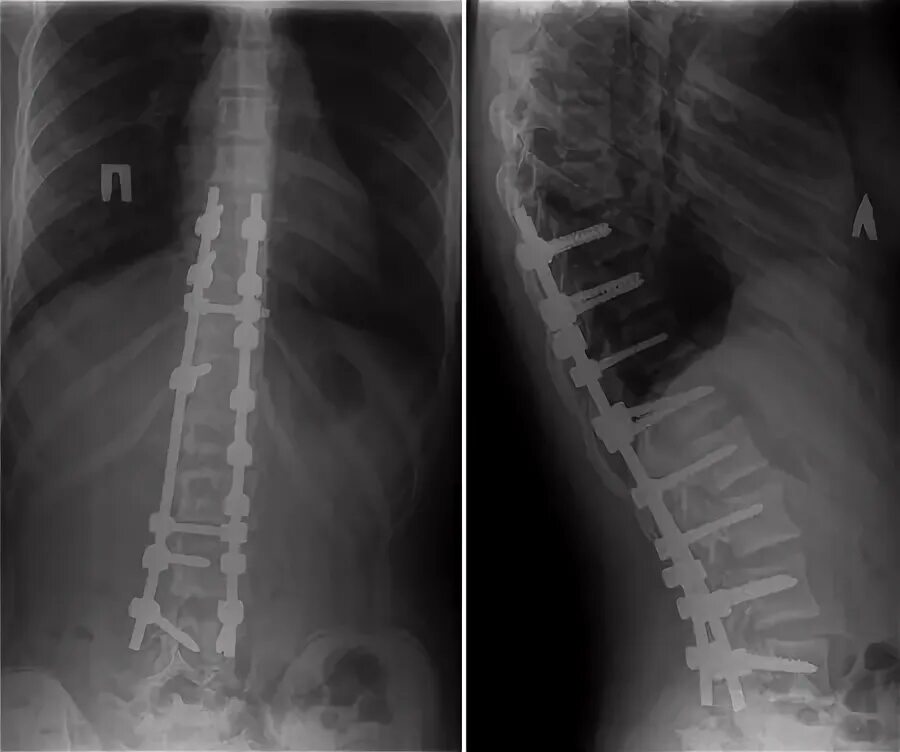

Операция по исправлению сколиоза